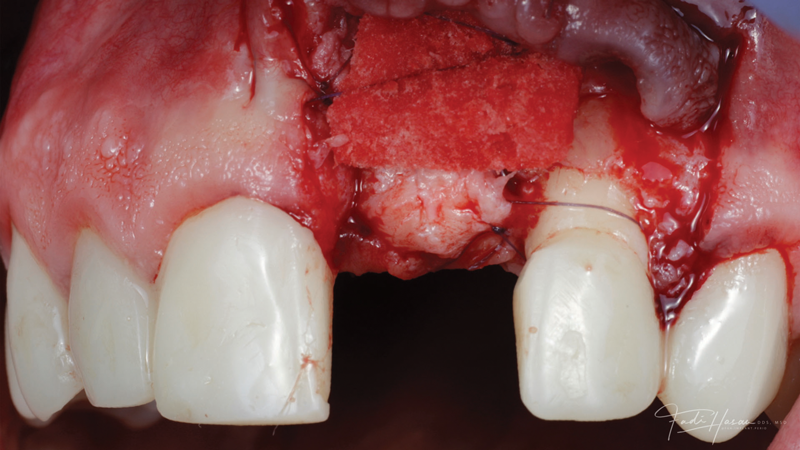

(3.) The crown was removed, and a partial thickness flap was reflected using a papilla-sparing incision design, which revealed that the implant was positioned too far facially and that its body was visible through a very thin layer of bone.

Figure 3

(4.) The crown was removed, and a partial thickness flap was reflected using a papilla-sparing incision design, which revealed that the implant was positioned too far facially and that its body was visible through a very thin layer of bone.

Figure 4